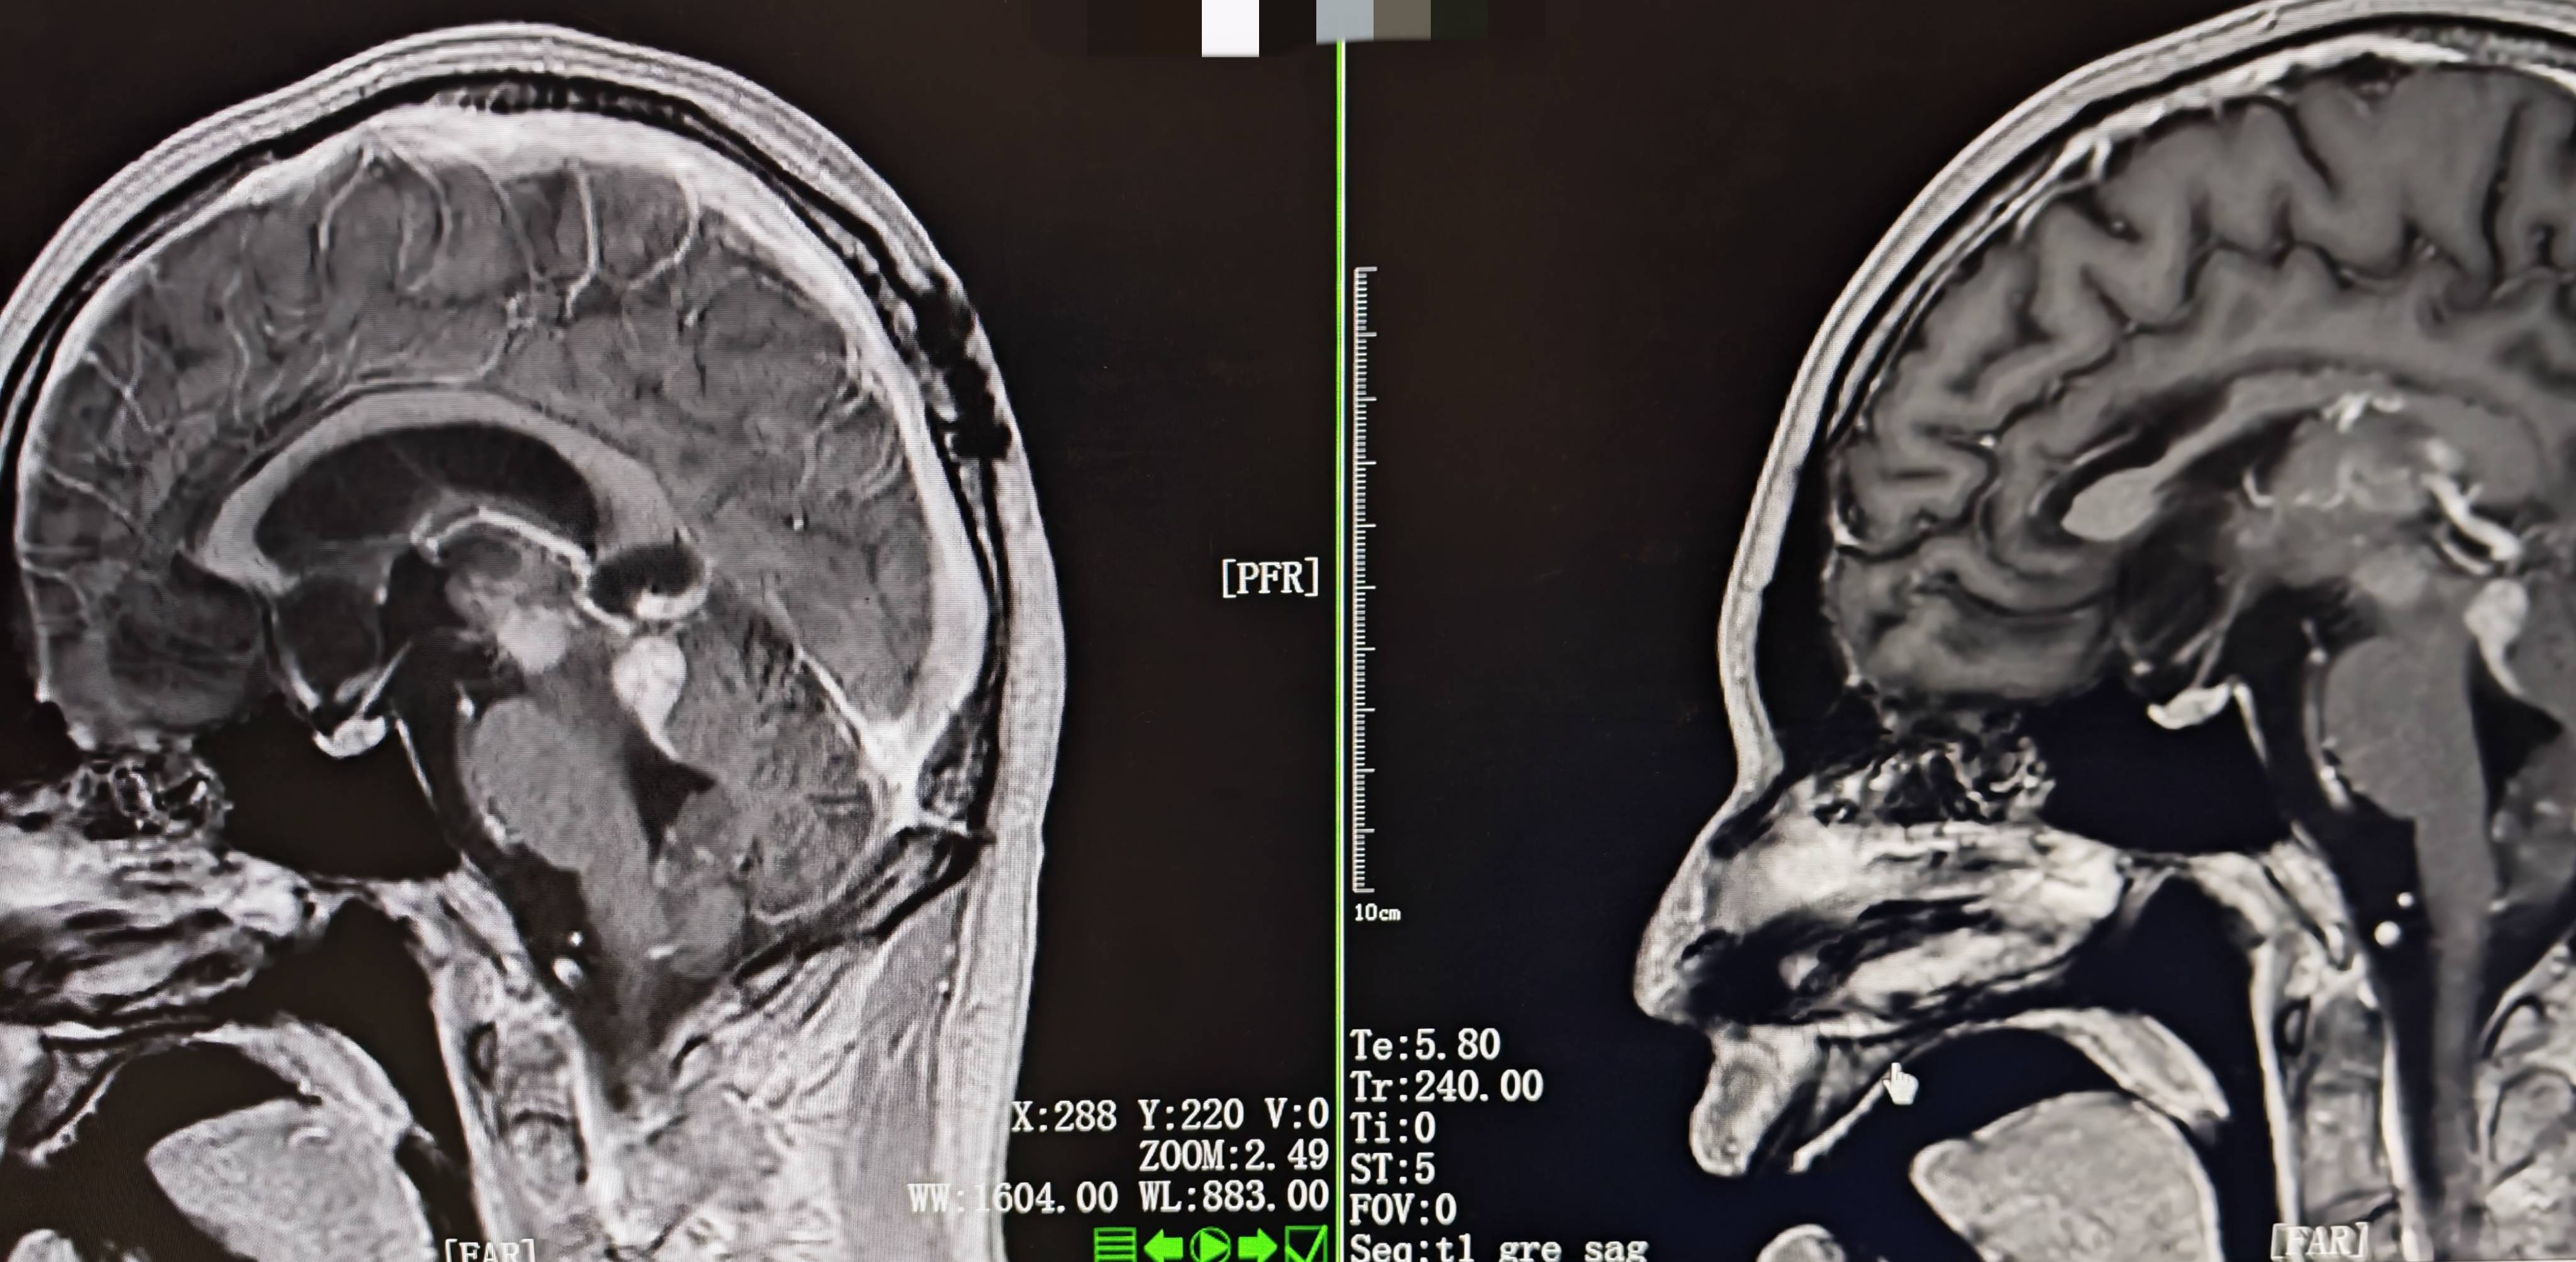

• 影像学(2025-08-06):头颅MRI示脑干及双侧丘脑病灶较前缩小,幕上脑室轻度扩张。

图 头颅MRI(左:2025年7月17日;右:2025年8月6日)

[2025-07-18] ➤ 第1周期化疗方案:贝伐珠单抗(100mg d1) + 去水卫矛醇(40mg d4-6) + 洛莫司汀(80mg d7);化疗后复查MRI示病灶较前明显缩小。

• 创新性采用"贝伐珠单抗+去水卫矛醇+洛莫司汀"联合方案,治疗后病灶显著缩小。